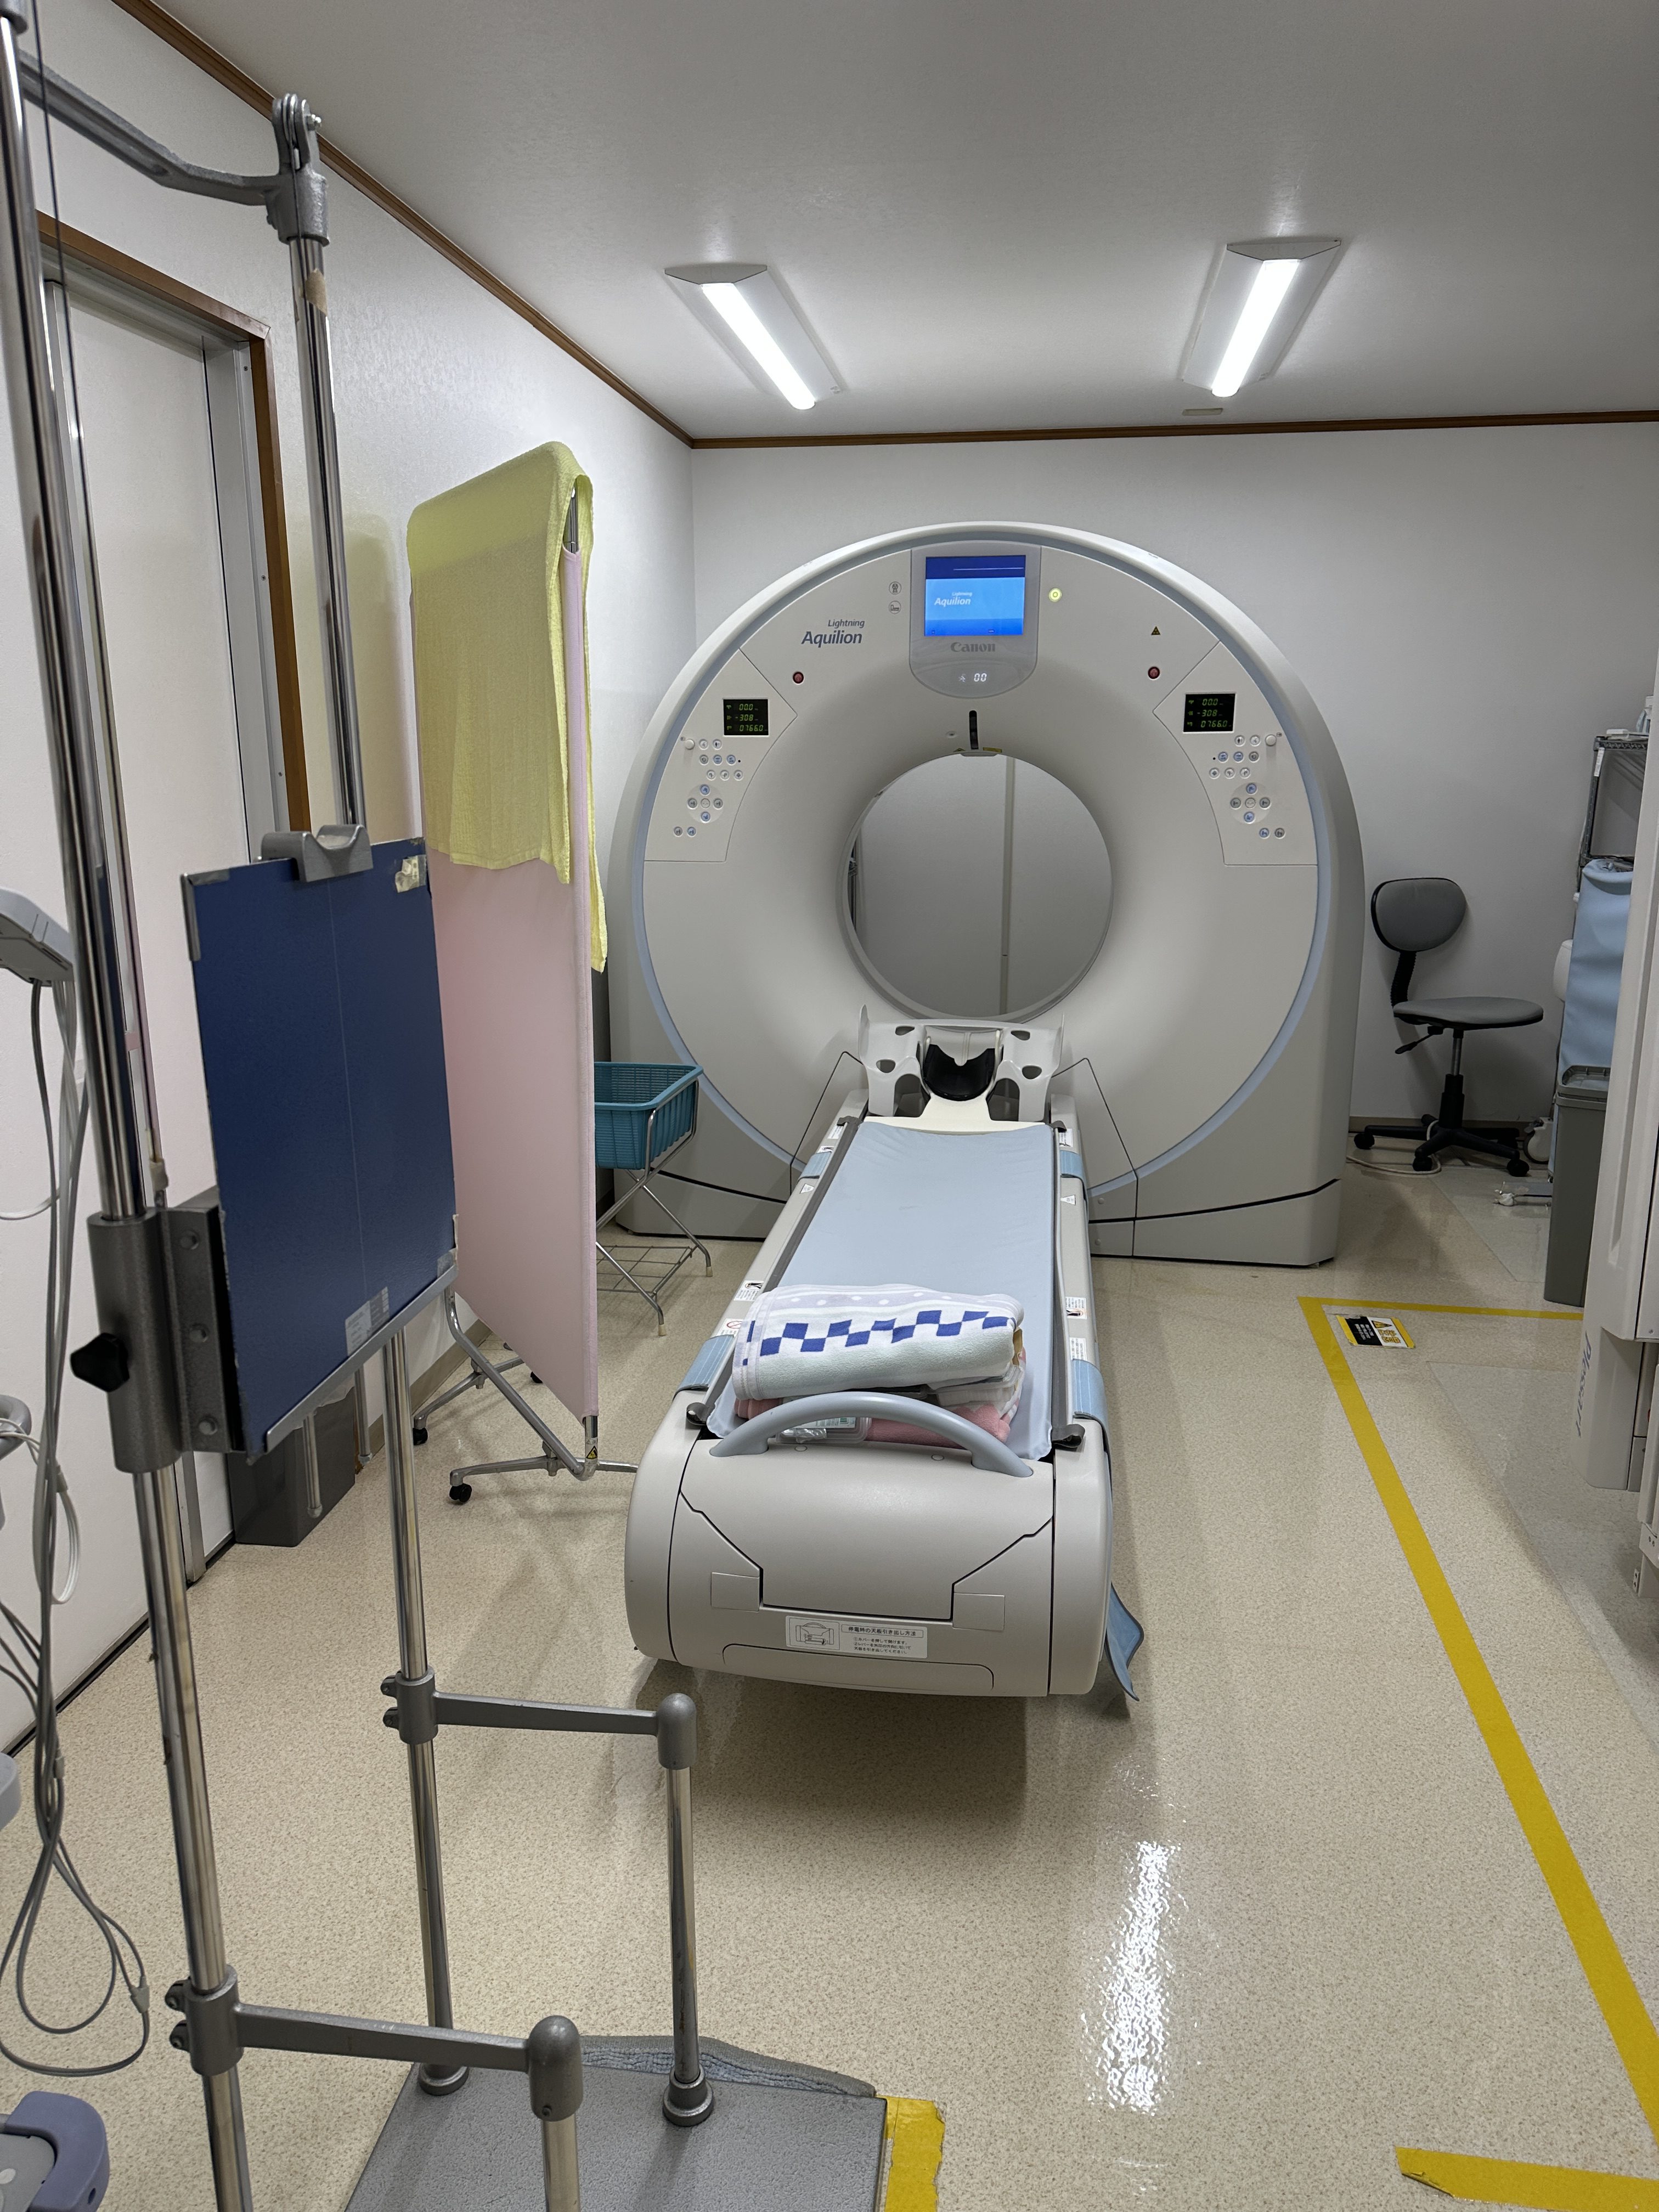

| Manufactured | : | November 2018 |

| Location | : | Japan (NEX325) |